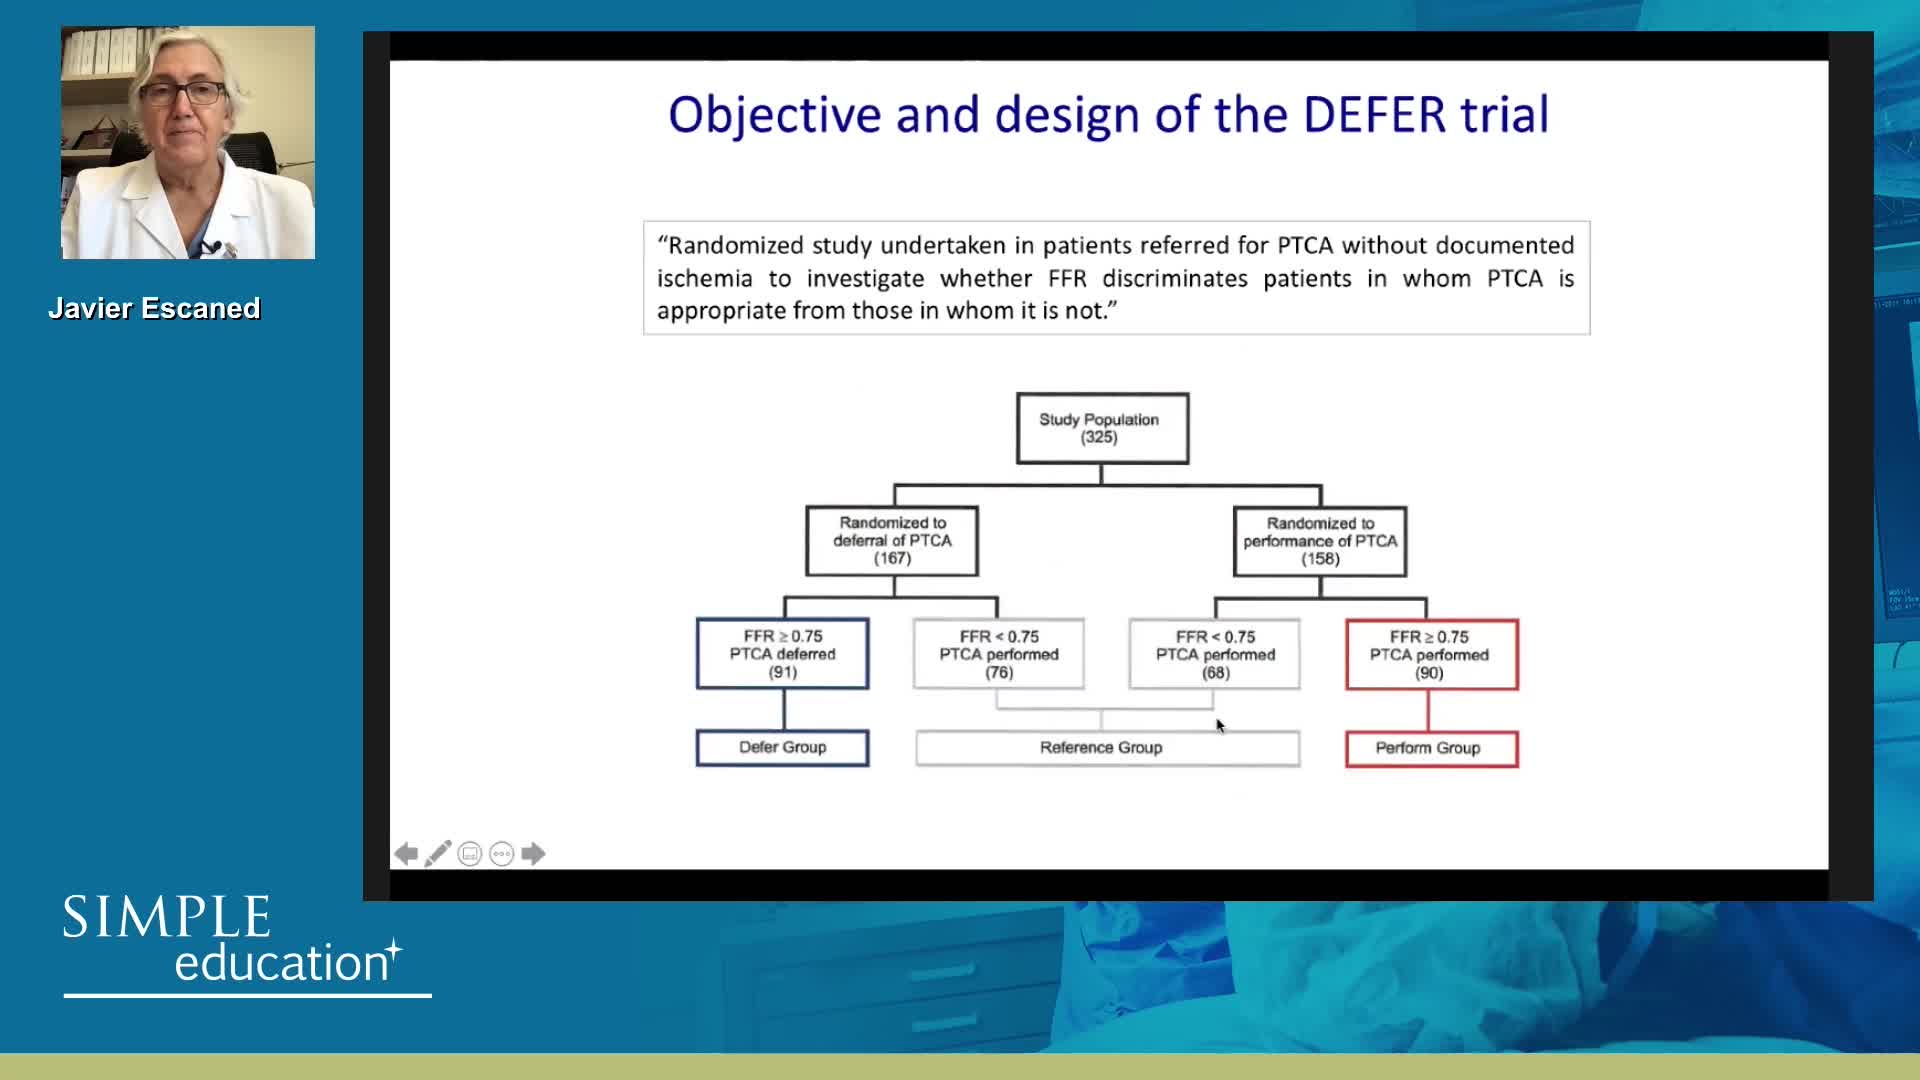

Best practices and personalised medicine in complex PCI - Prof Javier Escaned

Coronary physiology gate keeper or guide to coronary PCI? Rationale and design of DEFINE-GPS

20 year overview of clinical trial data to support the use of coronary physiology in revascularisation decision-making